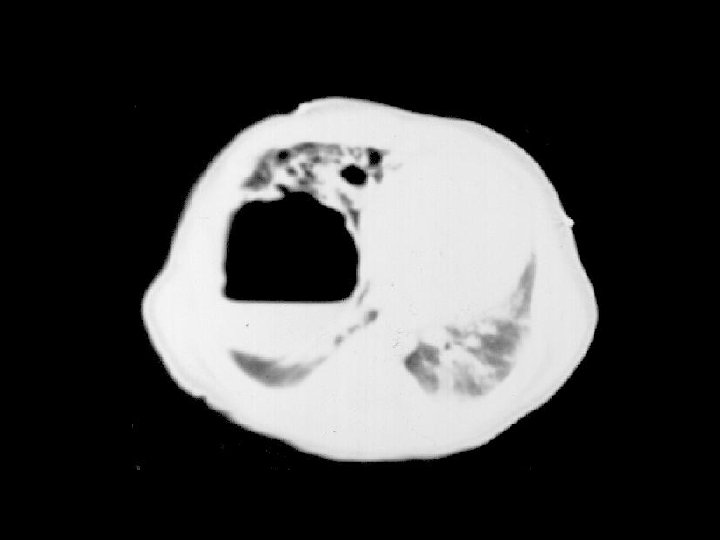

Lymphangioleiomyamatosis (LAM) • Findings: – hyperinflation with a reticular-nodular pattern – multiple thin-walled cysts • Rare dx of young women • present w/SOB, ptx, and chylous effusion • progressively fatal • ddx: – eosinophilic granuloma